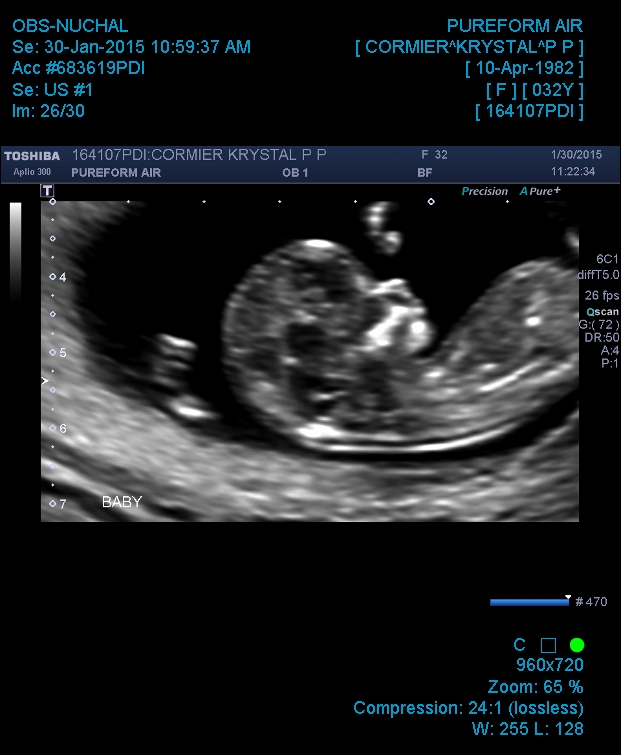

Attachment 23474Attachment 23475

cute baby :) can't really tell as cant see the end of the nub and baby is at a slight angle but a lovely profile shot, congratulations xx